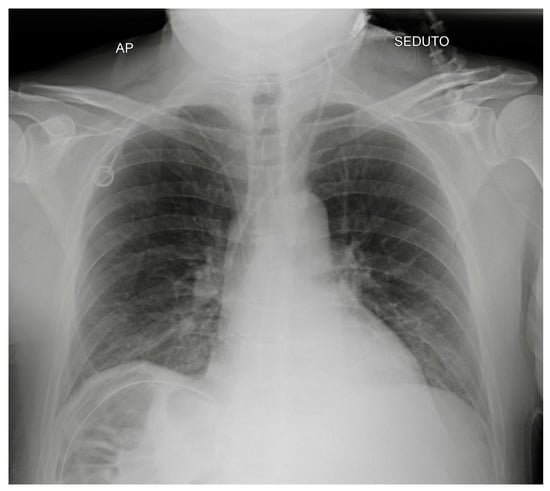

| Bronchus cannulation | Contralateral atelectasis, ipsilateral overinflation (risk of barotrauma, pneumothorax) | |